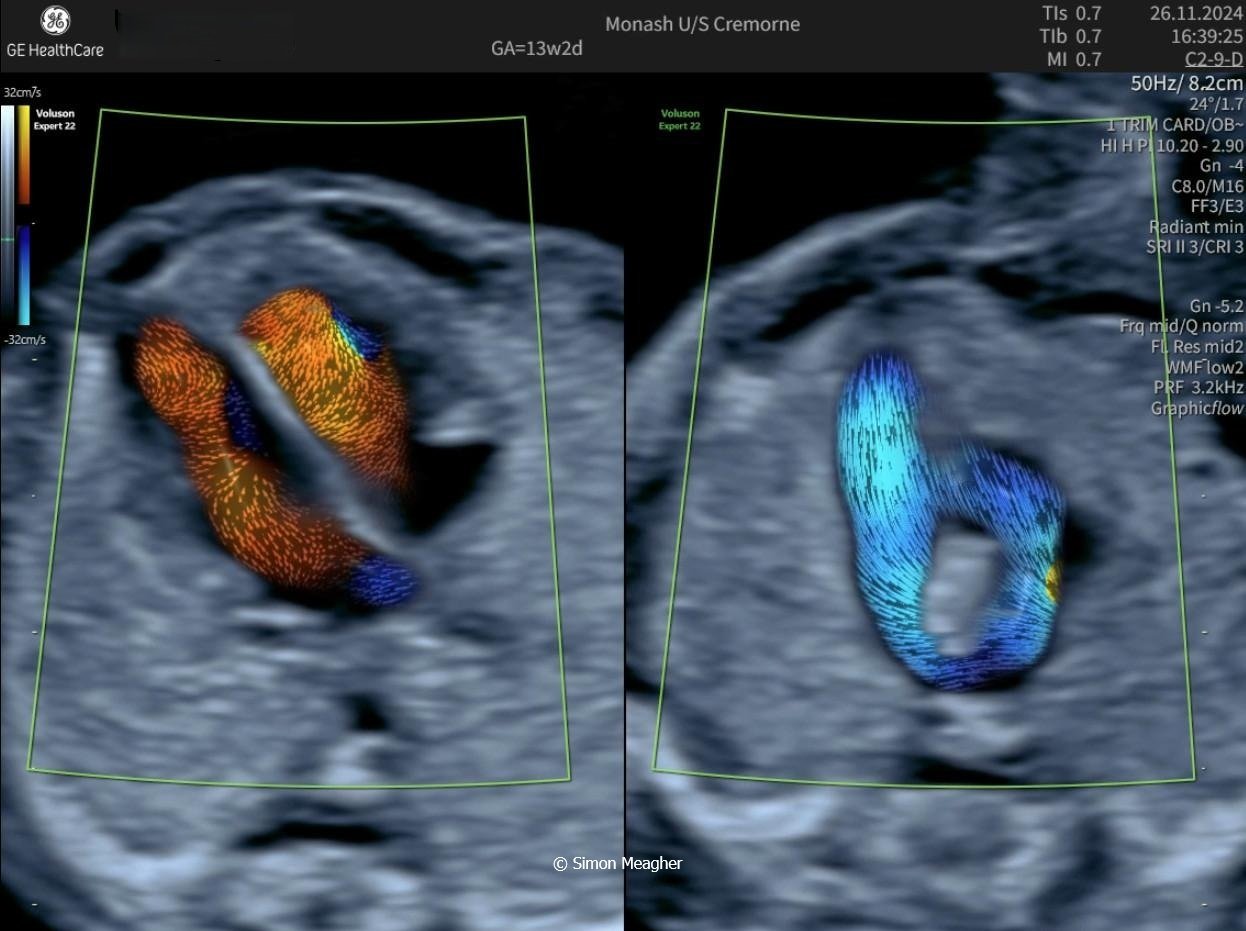

Join Professor Simon Meagher and leading experts for an intensive masterclass designed to transform your clinical practice.

This high-impact, one-day event delivers live scanning demonstrations, real-world case studies, and cutting-edge techniques across all trimesters.